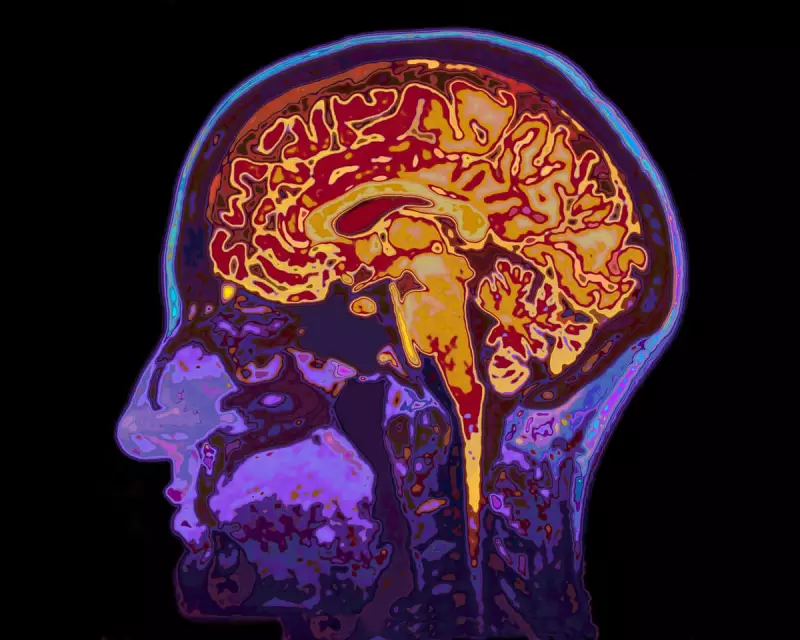

Cutting-edge research from leading neuroscientists reveals that sleep deprivation doesn't just make you feel groggy - it actively disrupts the delicate coordination between different brain networks responsible for maintaining focus. Using advanced brain imaging technology, researchers observed how tired brains struggle to maintain the synchronized activity necessary for sustained attention.

The study demonstrates that well-rested brains maintain a careful balance between the dorsal attention network (which handles focused concentration) and the default mode network (active during mind-wandering). In sleep-deprived individuals, this delicate balance collapses, causing the brain to flicker unpredictably between states of focus and distraction.